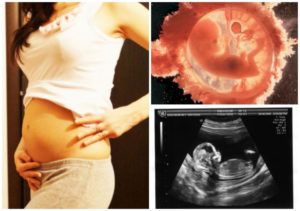

Размер тела ребенка достиг 8-10 см, вес – 20 г. Его можно сравнить с персиком.

На мониторе можно увидеть головку ребенка, на которой будут видны глаза с плотно сомкнутыми веками, ротик, уши. Также хорошо видны руки с ладошками, ножки, и, если повезет – можно увидеть предположительный пол будущего ребенка.

Хоть ребенок и активен, но во время УЗИ многие малыши становятся менее подвижными. Если во время УЗИ малыш будет активен, мама сможет увидеть, как он сжимает в кулачке пуповину или кладет палец в рот, сжимает губы, открывает рот и зевает.

К концу 13-ой акушерской недели беременности плод становится по размерам сравнимым с персиком. Это примерно 6,5 – 7,8 см от темени до копчика, 10-12 см полного роста. Будущий малыш сейчас весит около 20-30 гр. Головка увеличивается в диаметре почти до трех сантиметров.

- Уже отчетливо видно лицо. На снимках УЗИ можно рассмотреть черты будущего младенца. Правда, глаза еще довольно далеко посажены и сближаются постепенно. Глазные яблоки уже прикрыты веками. Голова уже немного приподнята над грудиной, поэтому просматриваются подбородок, носик и надбровные дуги. Уже очертились ушные раковины и мочки ушей.